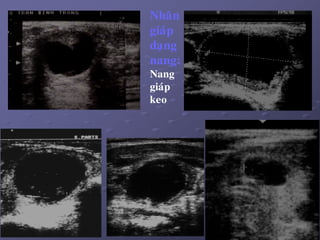

2/. Nhaân giaùp daïng nang:

a. Ñaëc tính:

 Nang giaùp thaät söï ít thaáy.

 Phaàn lôùn nang giaùp thöôøng gaëp laø nang keo do keát tuï

dòch keo trong caùc tuùi nang, dòch vaøng, seät. Khi coù xuaát

huyeát = nang giaû maùu (pseudo – heùmatique).

b. Hình aûnh SA: ña daïng, tuøy theo giai ñoaïn (tuoåi cuûa nhaân).

Löu yù: K gíap khoâng bao giôø bieåu hieän döôùi daïng nang hoøan toaøn.

Nhaân

giaùp

daïng

nang:

Nang

keo